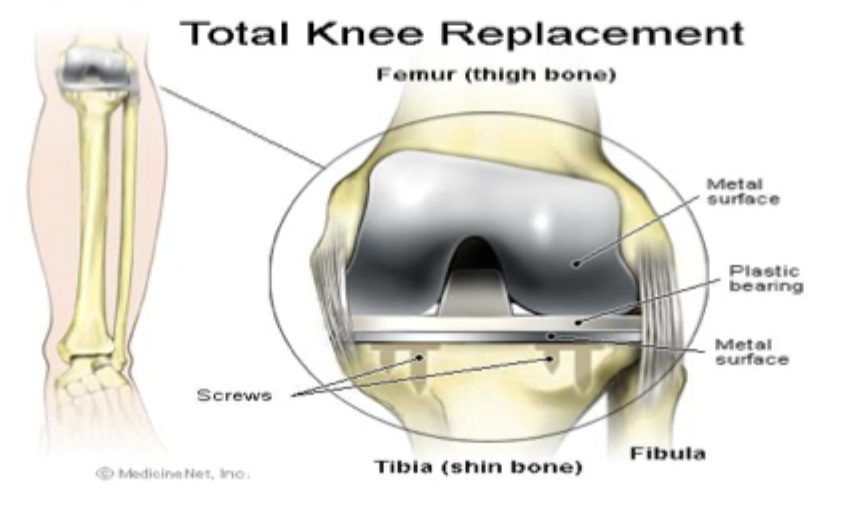

High-tibial osteotomy, joint arthroplasty, arthroscopic debridement

Operative management of OA

Core decompression (very early stages), vascularized bone grafting, osteotomy, joint replacement

Surgical management of AVN (depends on stage and joint)